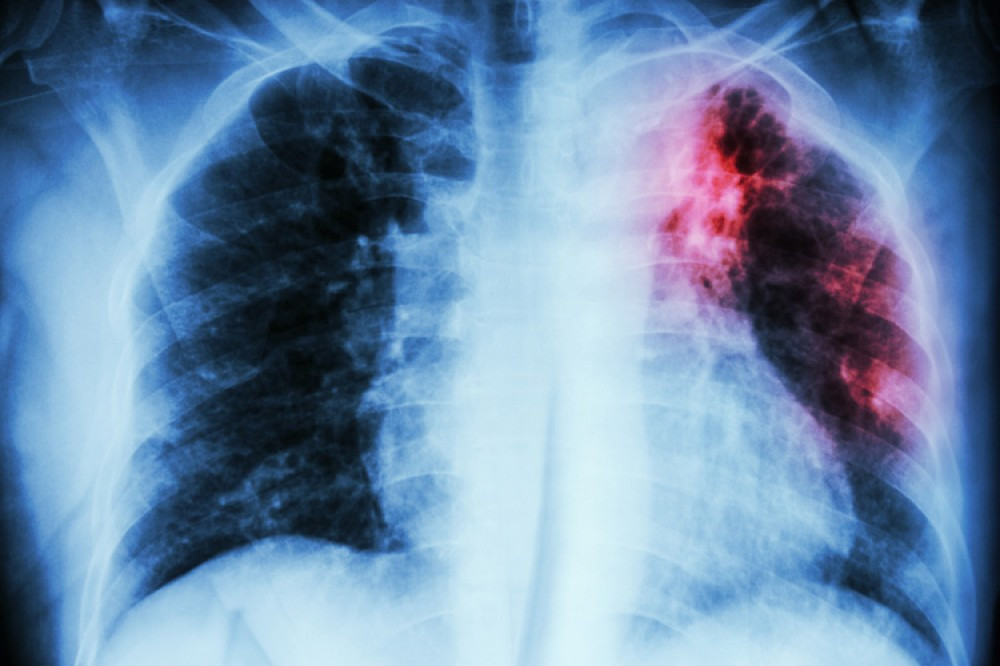

“Təəssüf ki, vərəm hələ də cəmiyyətdə qorxu və yanlış inanclar doğuran xəstəliklərdəndir”.

Onun sözlərinə görə, vərəm hava-damcı yolu ilə, yəni xəstə öskürəndə, asqıranda və ya danışanda havaya yayılan vərəm mikobakteriyaları vasitəsilə yoluxulur: